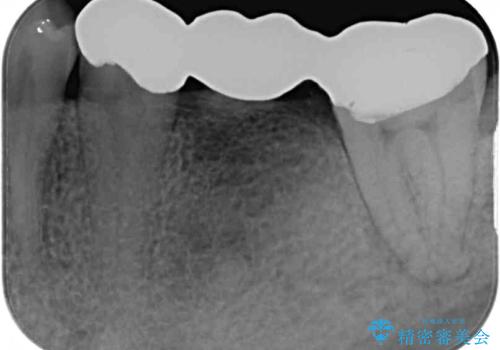

診察を行ったところ、奥の土台になっている歯は神経組織が失活しており、根尖部に病変があり、そこが原因で痛みを生じている状態でした。

根管治療を行うためにブリッジを除去したところ、むし歯が歯肉の奥深くにあまで及んでいたため、歯周外科処置によりむし歯が歯肉縁より浅い位置へと改善することとしました。

まずは奥歯の痛みを改善し、その後矯正治療を行い、最後にオールセラミックブリッジによる補綴治療を行うこととしました。